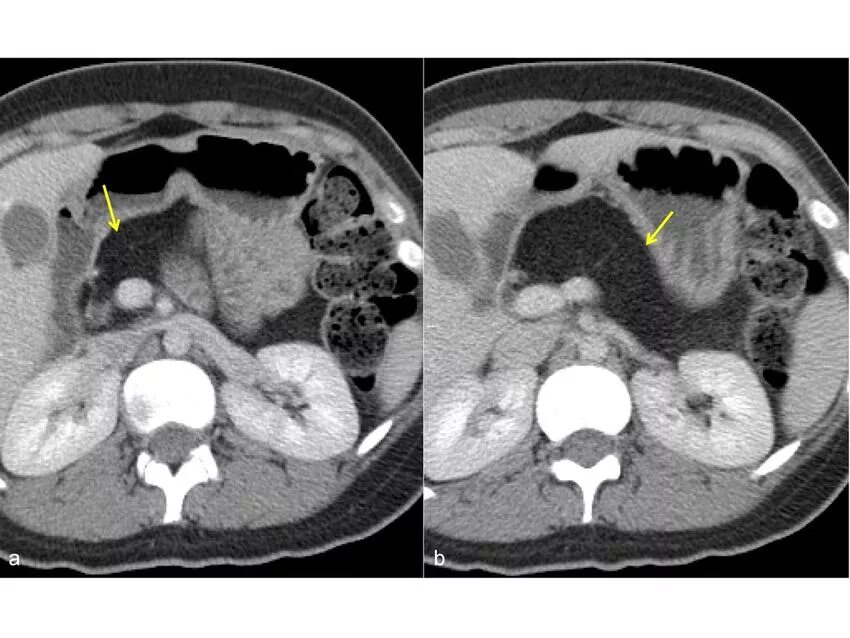

Липоматоз поджелудочной лечение лекарствами